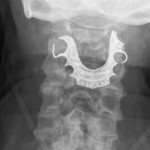

The man went to the emergency room because he was having a hard time swallowing and was coughing up blood. Doctors ordered a chest X-ray, diagnosed him with pneumonia and sent him home with antibiotics and steroids. It took another hospital visit before another X-ray revealed the problem: His dentures — a metal roof plate and three false teeth — lodged at the top of this throat.